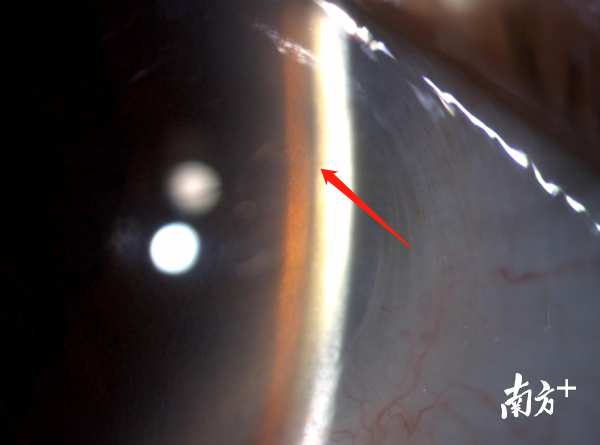

张先生属于慢性闭角型青光眼,右眼虹膜和角膜的间隙"房角"出现3°狭窄,左眼房角已出现粘连关闭,房水无法通过Schlemm管排出,引发青光眼。